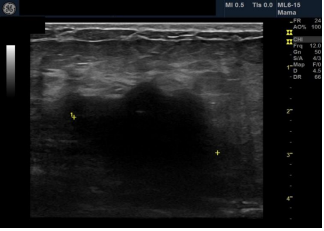

Female patient, black, 76 years old, G3P3, complaining of a lump in the right breast that had appeared 8 months ago. He has a history of admission to the intensive care unit 10 months ago due to an ischemic stroke, presenting left hemiparesis. Presents hypertension, hypothyroidism and dyslipidemia. Family history of father with prostate cancer. He presents sclerocalcification in the mitral and aortic valve on the echocardiogram. He presented clinical signs of an initial dementia process.Ultrasonography showed a heterogeneous image of 3.9/2.4/3.7cm in the union of the upper quadrants of the right breast, axillary lymph nodes with proportionality between cortex and hilum bilaterally BI-RADS 4 B BI-RADS 4 B.

Our patient died within 1 year after diagnosis, in line with reports of survival in 5, 10 and 15 years of 98.1%, 94.1% and 91.4%, respectively [3,16,17]. The literature describes stability of tumor size for 1 to 2 years, corroborating our case in which the tumor was practically stable during 1 year of follow-up [13]. There are cases in the literature of slow tumor growth over a period of 9 years in a patient who denied treatment [13]. A. heterogeneous image presentation on ultrasound is compatible with the aspect described in the literature [13].